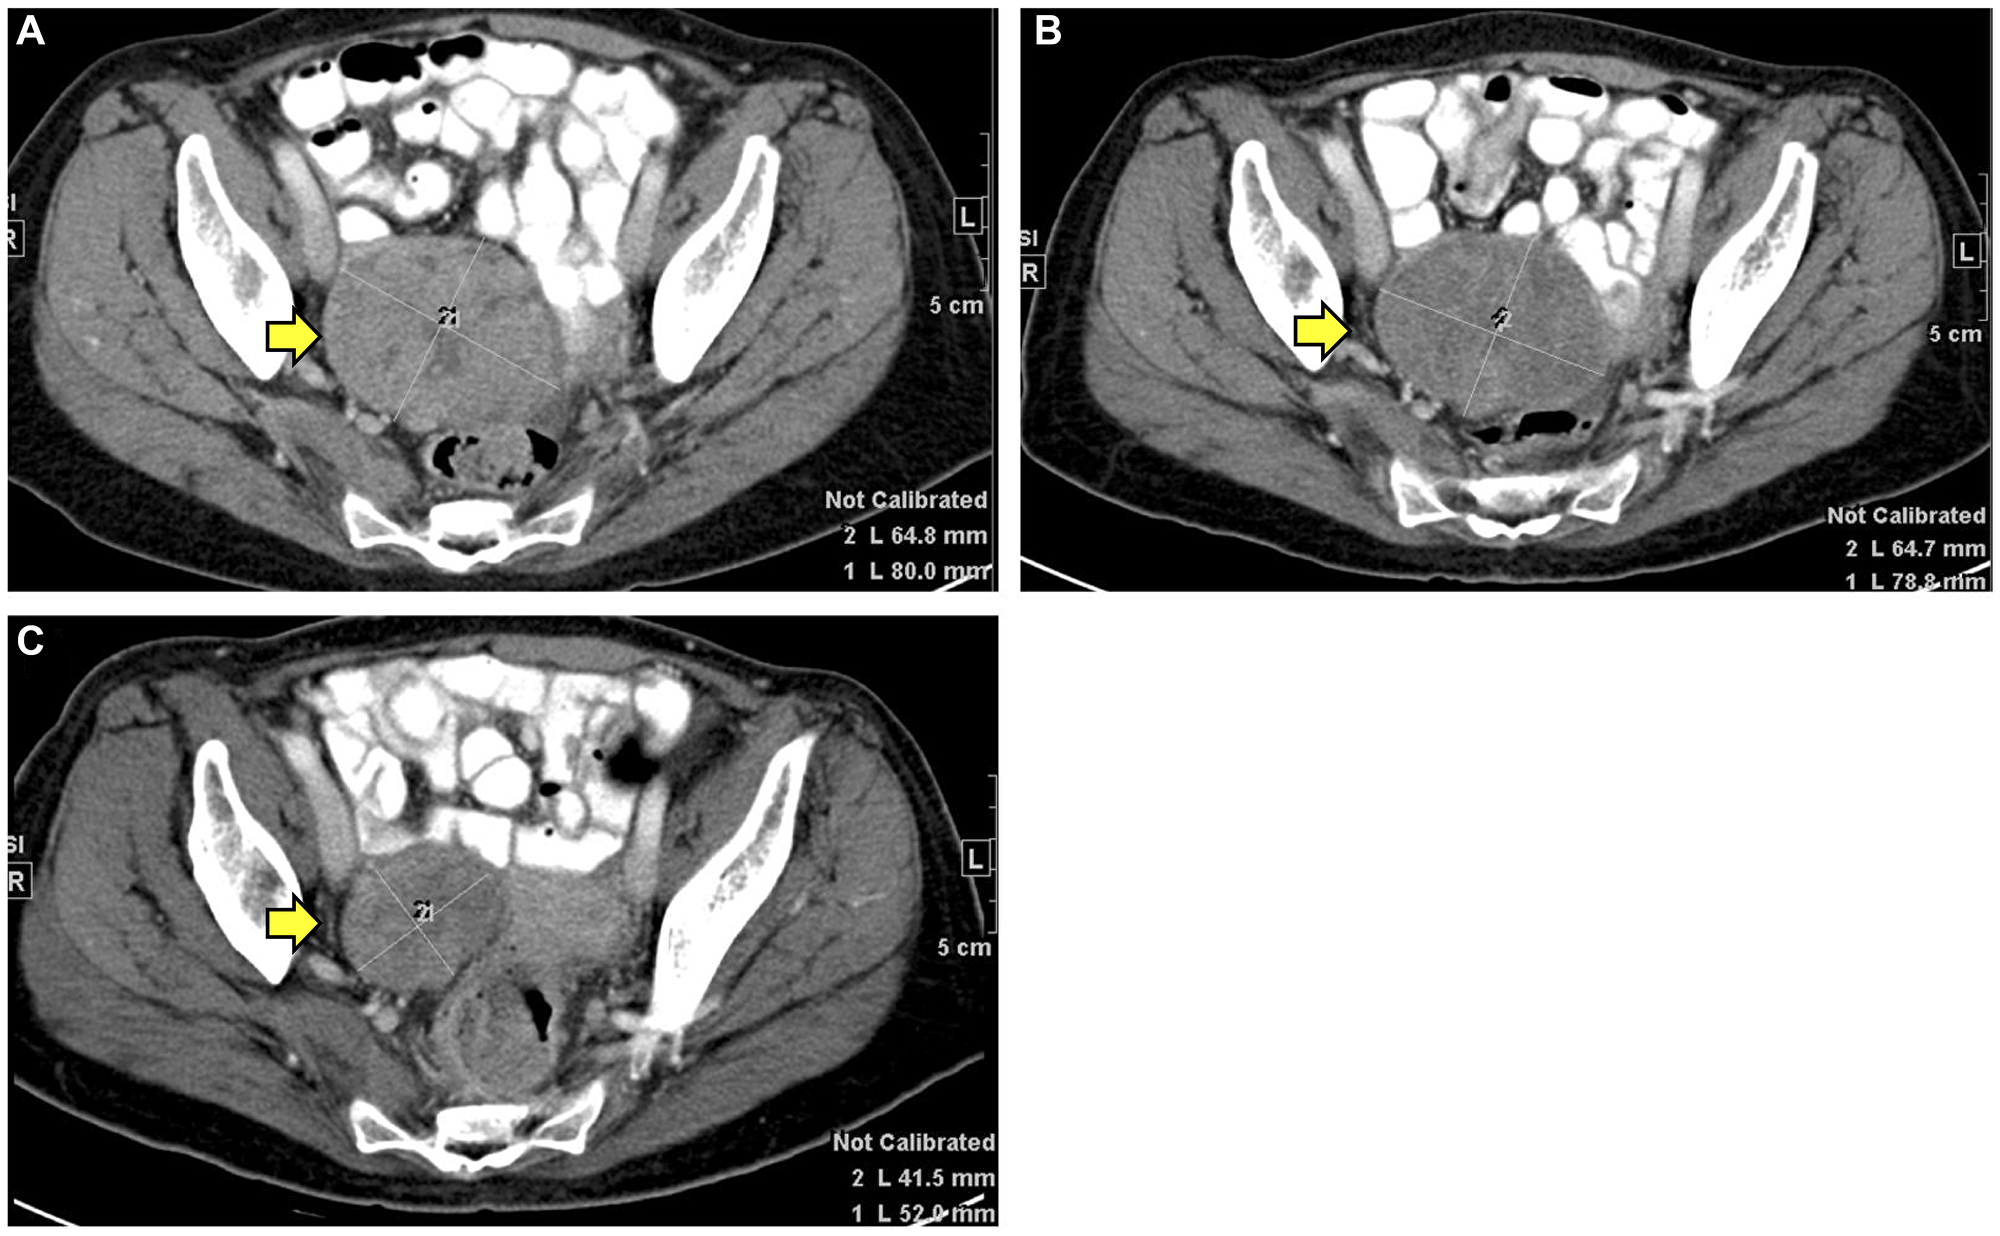

The radiological response data are described in Supplementary Table 2. Three patients did not have imaging information. None of the patients showed CR, nine patients (82%) showed PR, and two patients (18%) showed PD. Though these two patients had PD (patient #3 and #11), they demonstrated a biochemical response with a fall in CA 19-9 after starting immunotherapy, and hence were included in the analysis (Figure 3). Figure 4 depicts the imaging for a metastatic lesion in the pelvis of patient #9 before, at the start of, and at the maximal response of immunotherapy. The temporal trends in CA 19-9 following immunotherapy are shown in Figure 3. Nearly 67% (8/14 patients) showed stable CA 19-9 levels less than 100 U/ml throughout receipt of immunotherapy. 33% of patients (4/14 patients) had marked reduction in CA 19-9 levels; for instance, patient #3 showed reduction in CA 19-9 from 6418 U/ml to 274 U/ml at maximal response to immunotherapy.

CT imaging findings of patient #9

Figure 4: CT imaging findings of patient #9.

(A) before starting immunotherapy, (B) at the start of immunotherapy, and (C) at maximal response to immunotherapy.